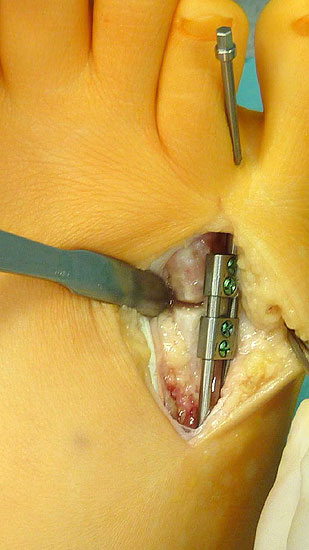

Das im Folgenden vorgestellte Operationsverfahren beschreibt die Kallusdistraktion von Metatarsalia nach den Prinzipien von Ilisarov 21 unter Verwendung eines internen, winkelstabilen Titan-Minifixateur (Klauser 2009). Der interne Distraktor ermöglicht während der Distraktions- und der Durchbauungsphase aufgrund seiner hohen Stabilität je nach Modell (18 mm, 23 mm) eine Verlängerung von bis zu 25 mm. Nach interner Anlage des Minifixateurs, meist lateral, kann über eine kontinuierliche Kallusdistraktion der Metatarsalebogen unter frühzeitiger Mobilisation im Gips oder Short-Walker rekonstruiert werden 15. Über einen interdigital und transcutan ausgeleiteten Aktivatorstab wird die Distraktion vom Patienten selber täglich morgens und abends durchgeführt. Zusätzlich vorliegende Strahlpathologien, wie zum Beispiel eine verkürzte Strecksehne oder ein kontraktes Metatarsophalangealgelenk können im Rahmen der Erstoperation ebenso therapiert werden wie z.B. ein Hallux valgus, ein Hallux valgus interphalangeus und/oder ein Digitus quintus varus (Klauser 2009). Nach Rekonstruktion des Metatarsalebogens wird in einem zweiten, kleinen Eingriff der Aktivatorstab über eine Spezialpinzette diskonnektiert und entfernt, wobei der Distraktor als interne Fixation belassen wird. Die Entfernung des Distraktors erfolgt in der Regel nach 9 – 12 Monaten, da es sich meist um angeborene kindliche Fehlbildungen handelt (Brachymetatarsie) und eine operative Intervention frühzeitig im Kindesalter erfolgen sollte (Klauser 2009).

• Laterale Implantation des Distraktors und damit besseres Anmodellieren entsprechend der ovalen Knochenstruktur des Os metatarsale und somit - sowie aufgrund der geringen Aufbauhöhe des Minifixateur - gute Weichteildeckung (Klauser 2009).

• Zweiter Eingriff: Diskonnektieren des transcutan ausgeleiteten Aktivator, falls möglich, über eine kleine Inzision von 1,5 bis 2 cm, in der Regel jedoch über Eröffnen der alten Schnittführung mit ggf. Strecksehnenverlängerung und erneutem Grundgelenk-Release sowie ggf. Ausleiten einer Penroselasche oder einer Gentamycin-Palacos-Minikette.